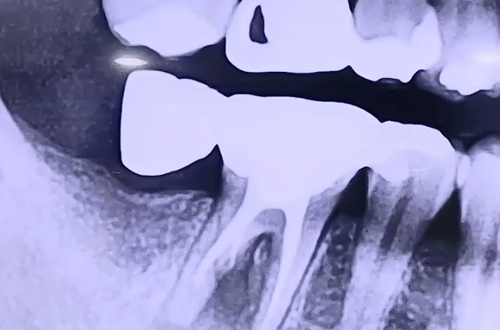

엑스레이를 찍어보니 예전에 받으셨다고 하는 어금니 보철 치료가 캔틸레버 브릿지라고 하는 브릿지 치료의 일종으로, 이를 뺀 뒤에 이가 없는 자리에 예쁘게 모양을 만들어 주기 위해서 옆에 있는 치아들에 이를 붙여서 걸어 얹어두는 것과 같은 브릿지입니다.

이런 치료는 예전에 임플란트 보급이 충분하지 않았을 때 많이 시행되었던 치료 방식인데요. 하지만 이렇게 만들어진 이는 저작운동을 하는 과정에서 옆에 붙어있는 치아에게 영향을 주어 결과적으로 치아가 상당히 상할 수 있기 때문에 지금은 진행되지 않는 치료입니다.

환자분께서는 그 결과로 치료 받은 어금니의 잇몸에 염증이 심해 극심한 통증에 이른 것이므로, 이 브릿지를 제거하고 그 자리에 안정적으로 한 치아를 한 개의 임플란트가 지탱할 수 있도록 임플란트 치료를 진행해 드렸습니다.